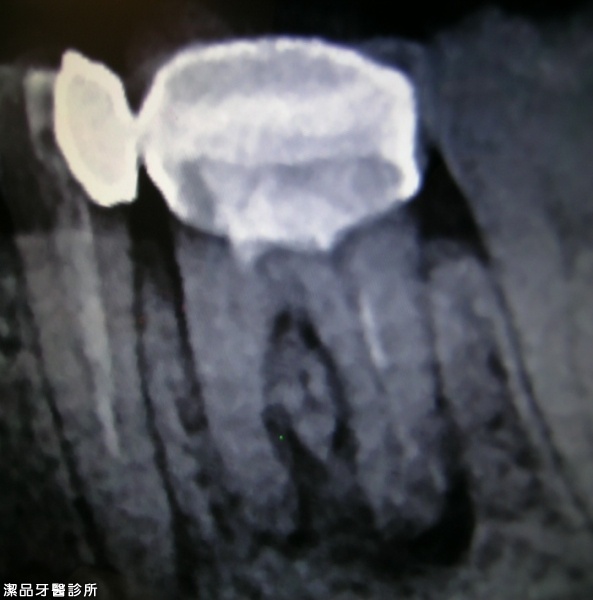

根管重新治療案例-002

案例簡述:

根管重新治療

治療前 骨因長期發炎而缺損